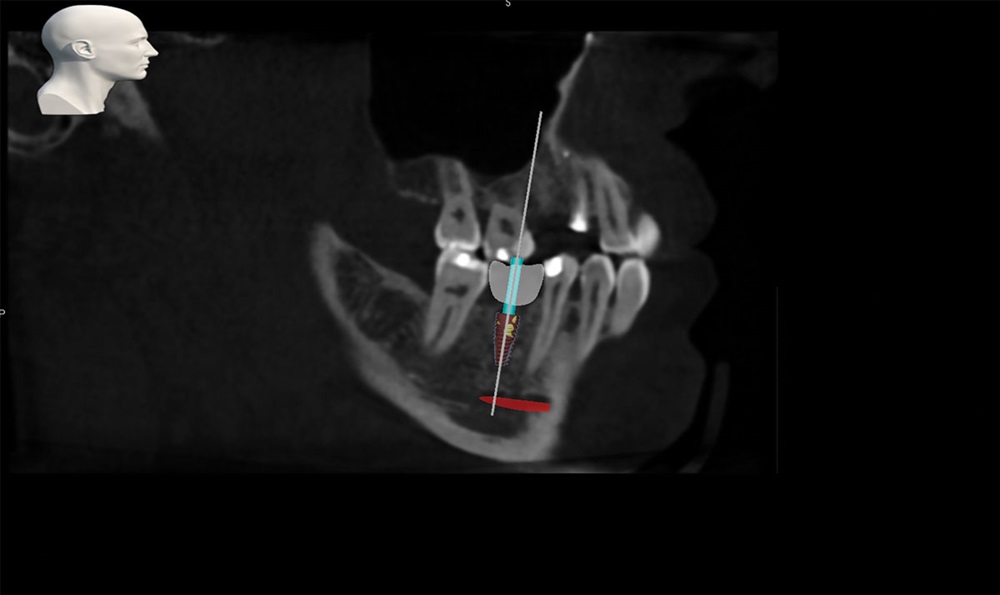

As another case example, see Figs. 11 and 12 showing a single implant placement.

Fig. 11: 3D plan for Case 2. Red shows nerve position.